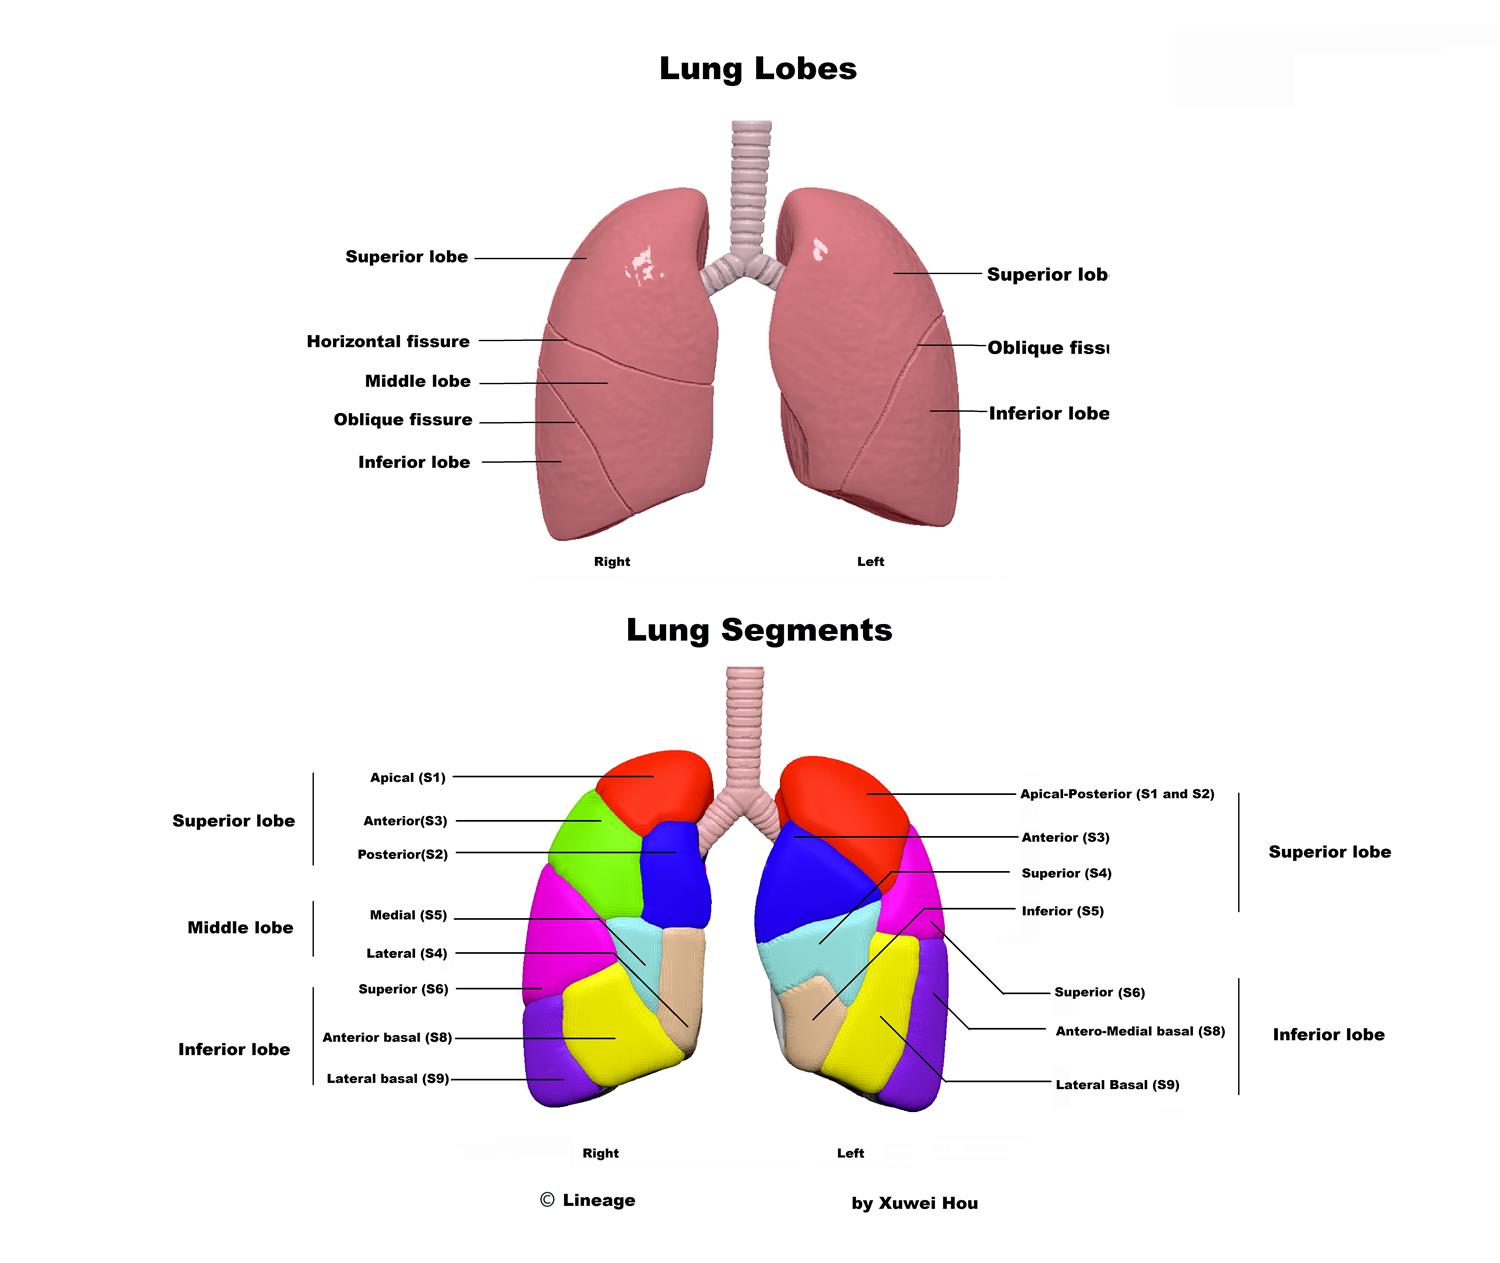

Bronchopulmonary Segments - Respiratory - Medbullets Step 1

step1.medbullets.com

step1.medbullets.com

segments bronchopulmonary lung lobes respiratory

Pin By Sonu On My Saves | Lung Anatomy, Medical Anatomy, Human Anatomy

www.pinterest.com

www.pinterest.com

lung gross

anatomy lungs lung segments pulmonary segmental tracheobronchial apex bronchial quizlet